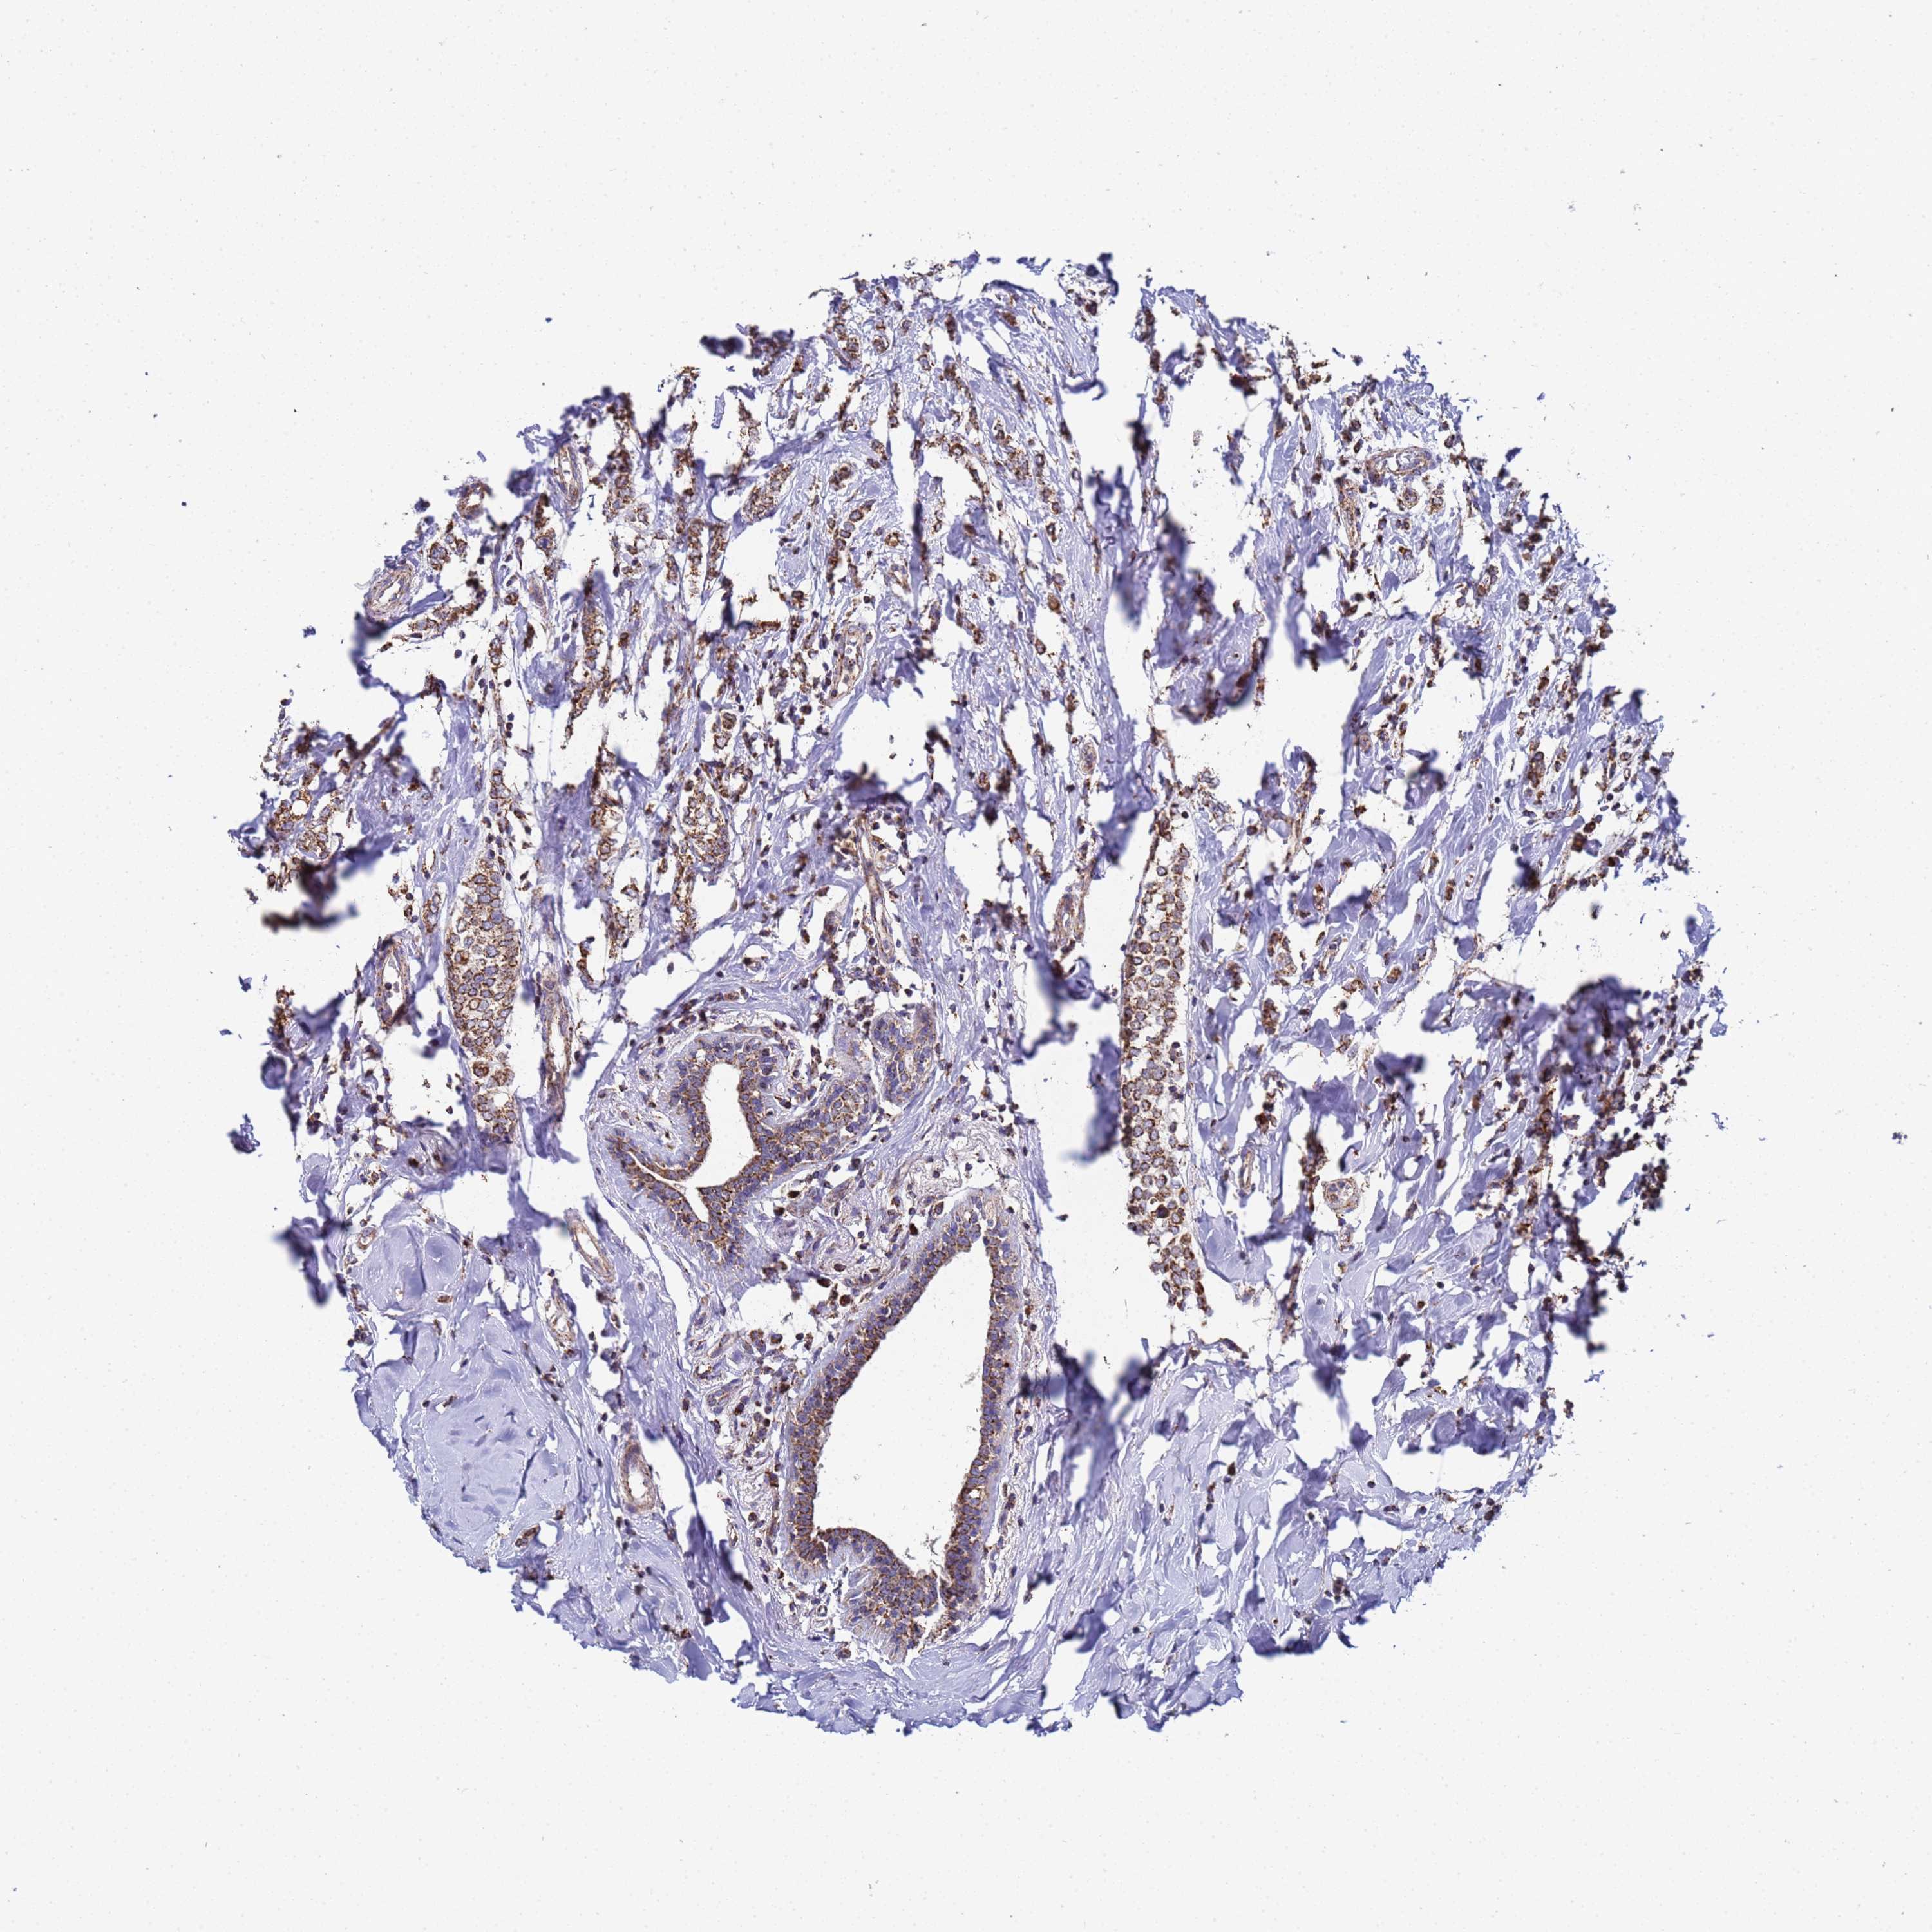

CANCER BREAST CANCER Show tissue menu

BRCA TCGA BRCA VALIDATION PROTEIN EXPRESSION

ANTIBODIES

AND

VALIDATION